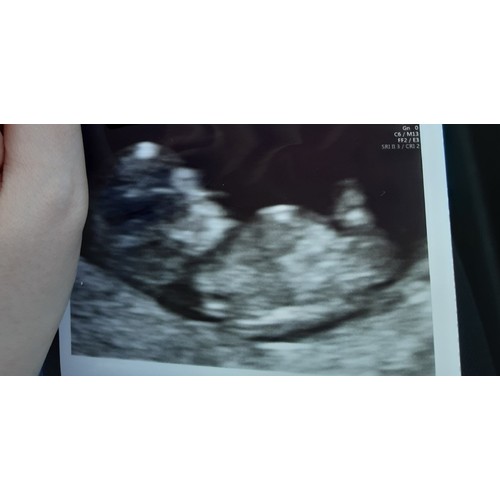

Ze maakte er al mooie koprollen bij! Nu een heerlijk beweeglijk meisje 🥰